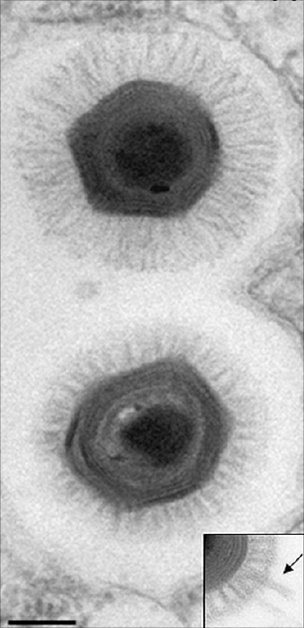

Professor Ruth Itzhaki and her team at the University's Faculty of Life Sciences have investigated the role of herpes simplex virus type 1 (HSV1) in AD, publishing their very recent, highly significant findings in the Journal of Pathology.

Most people are infected with this virus, which then remains life-long in the peripheral nervous system, and in 20-40% of those infected it causes cold sores. Evidence of a viral role in AD would point to the use of antiviral agents to stop progression of the disease.

The team discovered that the HSV1 DNA is located very specifically in amyloid plaques: 90% of plaques in Alzheimer's disease sufferers' brains contain HSV1 DNA, and most of the viral DNA is located within amyloid plaques. The team had previously shown that HSV1 infection of nerve-type cells induces deposition of the main component, beta amyloid, of amyloid plaques. Together, these findings strongly implicate HSV1 as a major factor in the formation of amyloid deposits and plaques, abnormalities thought by many in the field to be major contributors to Alzheimer's disease.

HSV1 is ubiquitous, identified in approximately 90% of adults. Normally, an infection with HSV1 occurs in infancy, but the virus remains lifelong in the peripheral nervous system in a latent, inactive state. HSV1 can be reactivated later in life by stress, immunosuppression, fever or ultraviolet light exposure; HSV1 is the virus that causes cold sores. Researchers postulate that if HSV1 reaches the brain, the virus could cause damage consistent with AD. Likewise, HSV1 is already identified as the cause of herpes simplex encephalitis, a rare but serious brain disorder, which leaves survivors with memory loss and a loss of cognitive function, just as AD does.

Two hallmarks of AD are the presence of amyloid plaques and neurofibrillary tangles in the brain. Beta-amyloid, the primary component of the plaques, accumulates in the presence of HSV1 infections. Further, 90% of plaques evaluated from AD brains contained HSV1, and 72% of the virus DNA was associated with plaques; in normal, aged brains, which contain amyloid plaques at a much lower frequency than AD brains, 80% of the plaques contained HSV1, but only 24% of the viral DNA was plaque-associated. In normal brains, it is likely that there is a lesser production or greater removal of beta-amyloid, so it is less likely that HSV1 would be able to interact destructively inside the brain. Basically, HSV1 infection likely induces changes in gene expression in the brain, through its inflammatory and oxidative processes, that are damaging to the brain.